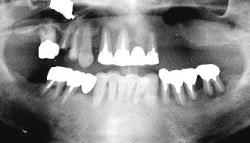

| 関西から通っている患者様です。 近々お嬢様の結婚式があるため、その前に上下共、All-on-4で治療して欲しいと来院されました。 右下親知らずは埋伏歯なので残してあります。 |